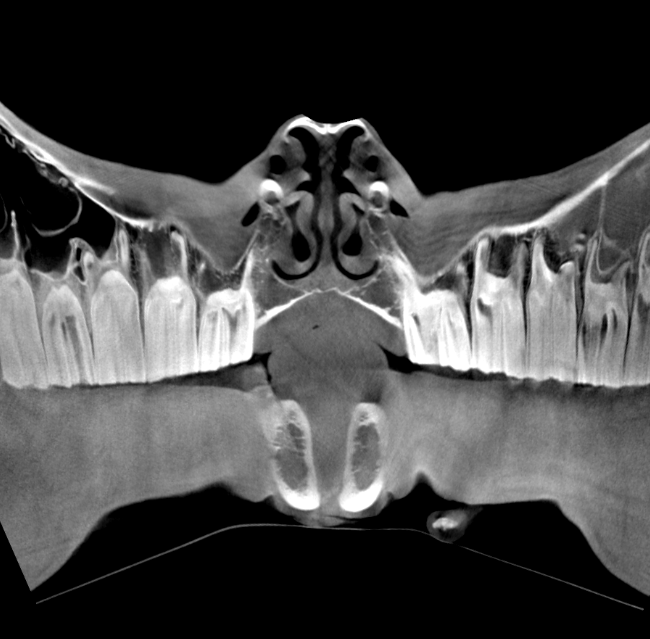

Our High Definition Volumetric Imaging (HDVI) technology represents the most advanced stage of Flat Panel CT technology. It offers exceptional diagnostic imaging for both hard and soft tissues, in diagnostic settings and intraoperative theaters. It is the gold standard for orthopedic applications.

Pegaso enhances safety and usability by enabling the scanning of a standing horse’s head, neck, and limbs.

Pegaso scans head, neck and limbs of the standing horse